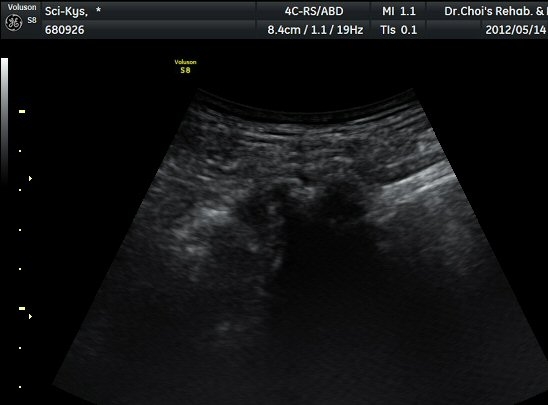

ŽÃËÀÚ¸¦ ¾à°£ ±ÙÀ§ºÎ·Î À̵¿ÇÏ´Ï °æ°è°¡ ºÒºÐ¸íÇÑ »À°¡ Á°ñ½Å°æ ¿ÜÃø¿¡¼­ µ¹ÃâÇϸ鼭

Á°ñ½Å°æÀ» ³»ÃøÀ¸·Î ½ÉÇÏ°Ô ÀüÀ§½ÃŲ´Ù(±×¸² 4, 5).